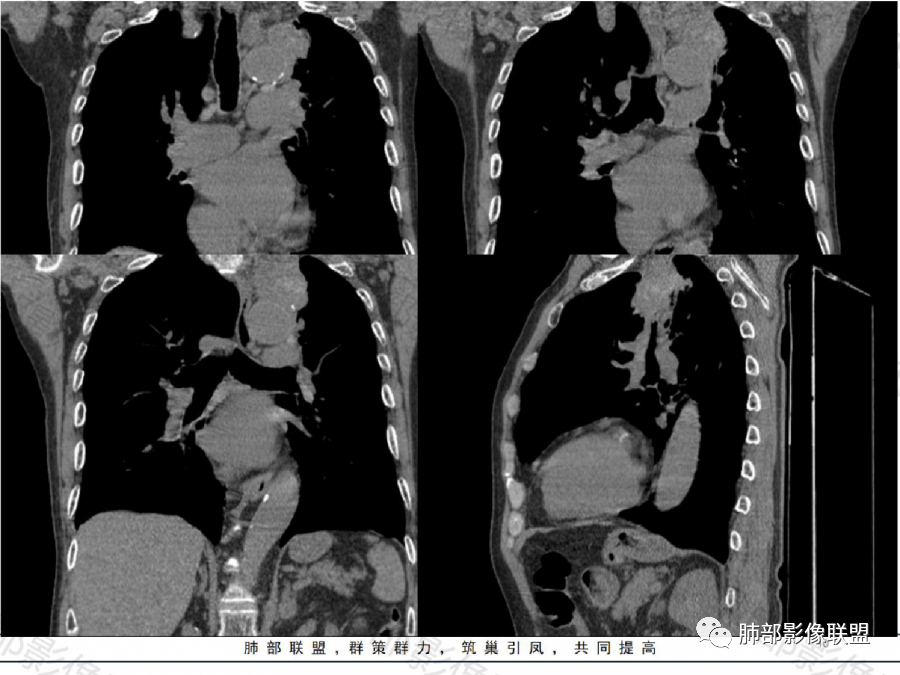

影像表现特点:左肺上叶纵隔旁主动脉弓上方实性肿块影,不规则,膨胀性生长,有棘状突起及收缩,肿块内密度不甚均匀,隐约见小钙化灶。周围具有一定的分叶及长短不一的毛刺征象,外围有小斑片影。矢状位显示支气管截断。增强扫描病灶不均匀强化,内部见小片状的坏死,呈典型的“沼泽样”改变。总体分析恶性征象更多。支持肺癌-鳞癌,支气管截断具有强烈提示意义。